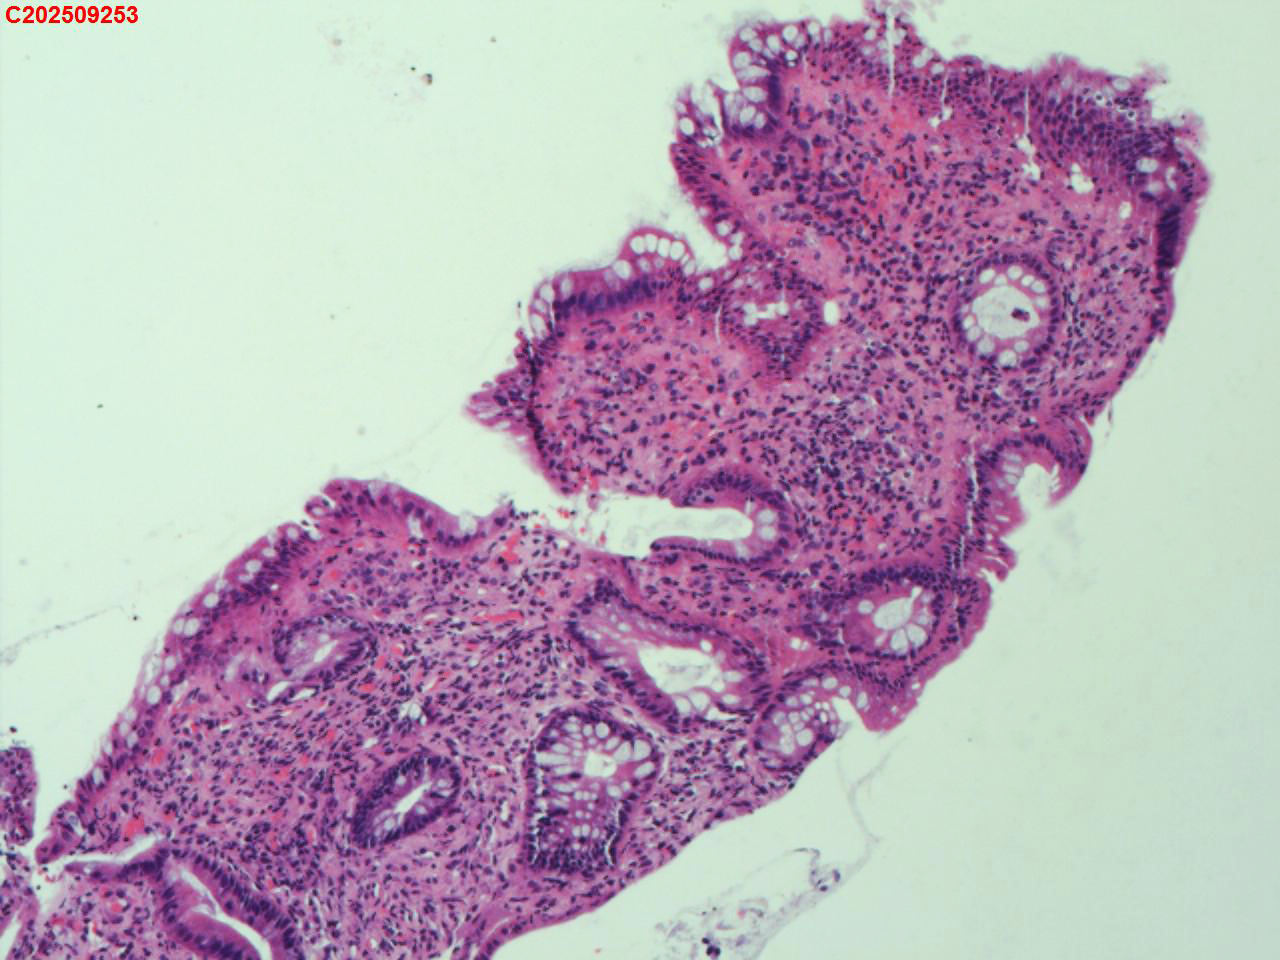

降结肠粘膜

性别

男

年龄

52岁

临床诊断

溃疡性结肠炎

一般病史

溃疡性结肠炎病史3年

标本名称

大体所见

降结肠多发鹅卵石样改变,多发糜烂。

图2